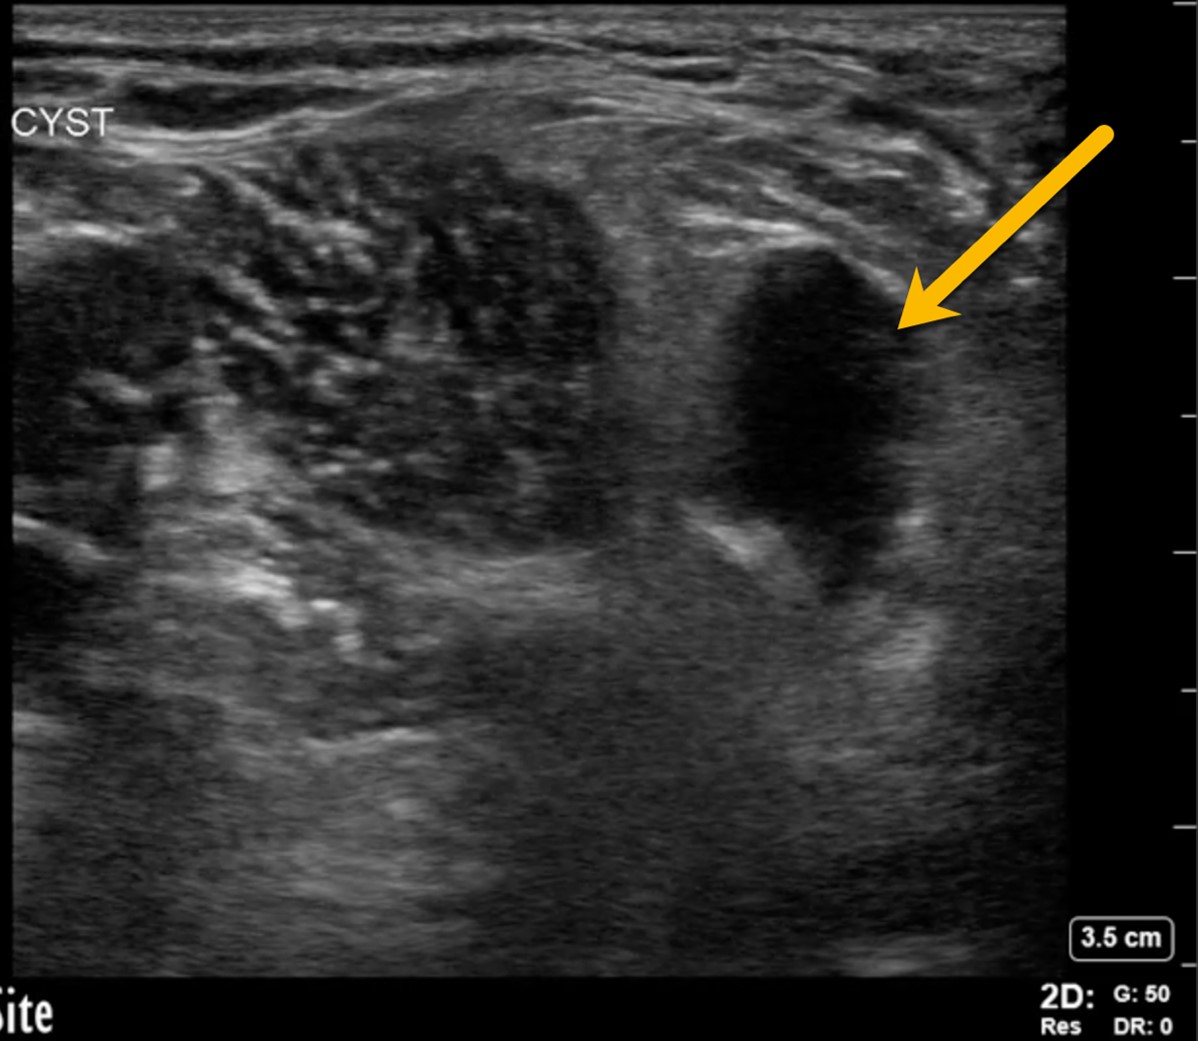

Using the high-frequency linear probe, typical views are obtained superior and inferior to the patella, as well as medial, lateral, and posterior to the knee joint. Views superior and inferior to patella assess for the integrity of the quadriceps and patellar tendons, the patella, as well as presence of knee effusion. Normal examination of the overlying skin and absence of cobblestoning of the soft tissue on ultrasound lessens the likelihood of cellulitis and abscess. Figure 1 shows the anterior ultrasound view of the knee, the patella. An intact patella should demonstrate the uninterrupted hyperechoic curvature of the cortical surface. In figure 1, we see an unmistakable cortical disruption (between the two red arrows), indicating a patellar fracture. Knee effusions will appear as an anechoic collection, indicated by the blue arrow, deep to the tendons. (Fig. 2) Medial and lateral views can also demonstrate effusions. Complex effusions such as hemarthrosis appear as hypoechoic collections if clotting has occurred. Figure 3 demonstrates a traumatic hemarthrosis identified by the green arrow. Figure 4 shows another simple knee effusion, indicated by the green arrow, without a history of trauma. Aspiration in the emergency department or office can be useful in directing therapy. In Figure 4, we see the needle approaching the effusion from the left side of the screen highlighted by the red arrow. Lastly, the posterior aspect of the knee contains the popliteal vessels. The popliteal vessels should be identified by Color Doppler, allowing differentiation from the non-vascular structures. Figure 5 shows a cystic non-compressible, anechoic structure without internal echoes within the popliteal fossa highlighted by the yellow arrow.

Figure 5